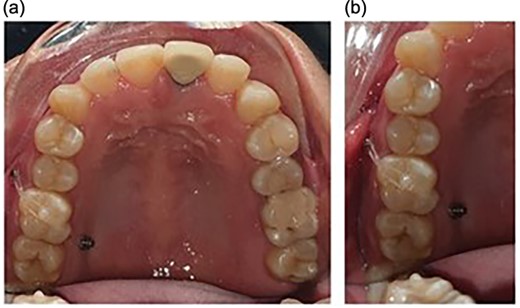

Maxillary molar intrusion 4 mm above the occlusal plane (Fig. 3).

Panoramic radiographs recorded at regular intervals showed that the lamina dura around the molar was intact and no root resorption was observed.